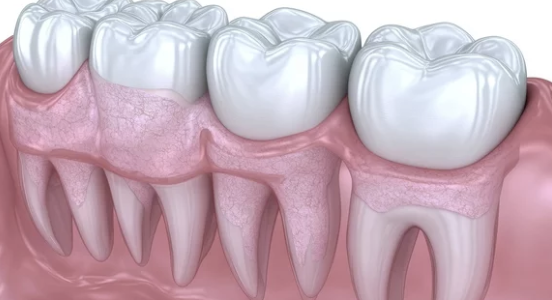

치아를 지탱해주는 잇몸은 구강 건강의 핵심입니다. 그런데 나이가 들거나 잘못된 칫솔질, 치주염 등의 원인으로 잇몸이 점차 아래로(혹은 위로) 내려앉는 현상, 즉 치은퇴축(잇몸퇴축)이 발생할 수 있습니다. 잇몸이 내려앉으면 치아 뿌리가 노출되고, 시린 증상이나 치아 흔들림, 심한 경우에는 치아 상실로도 이어질 수 있습니다. 이번 글에서는 잇몸이 내려앉을 때 나타나는 증상, 원인, 복원치료법, 예방 및 관리법까지 폭넓고 자세히 정리해드립니다.

잇몸이 아래로 또는 위로 내려가 치아 뿌리가 드러나는 현상은 치은퇴축(Gingival Recession)이라고 하며, 다음과 같은 다양한 원인으로 발생할 수 있습니다.

치은퇴축은 심할 경우 치아를 지지하는 치조골까지 손상시켜 결국 치아가 흔들리거나 빠질 수 있습니다.